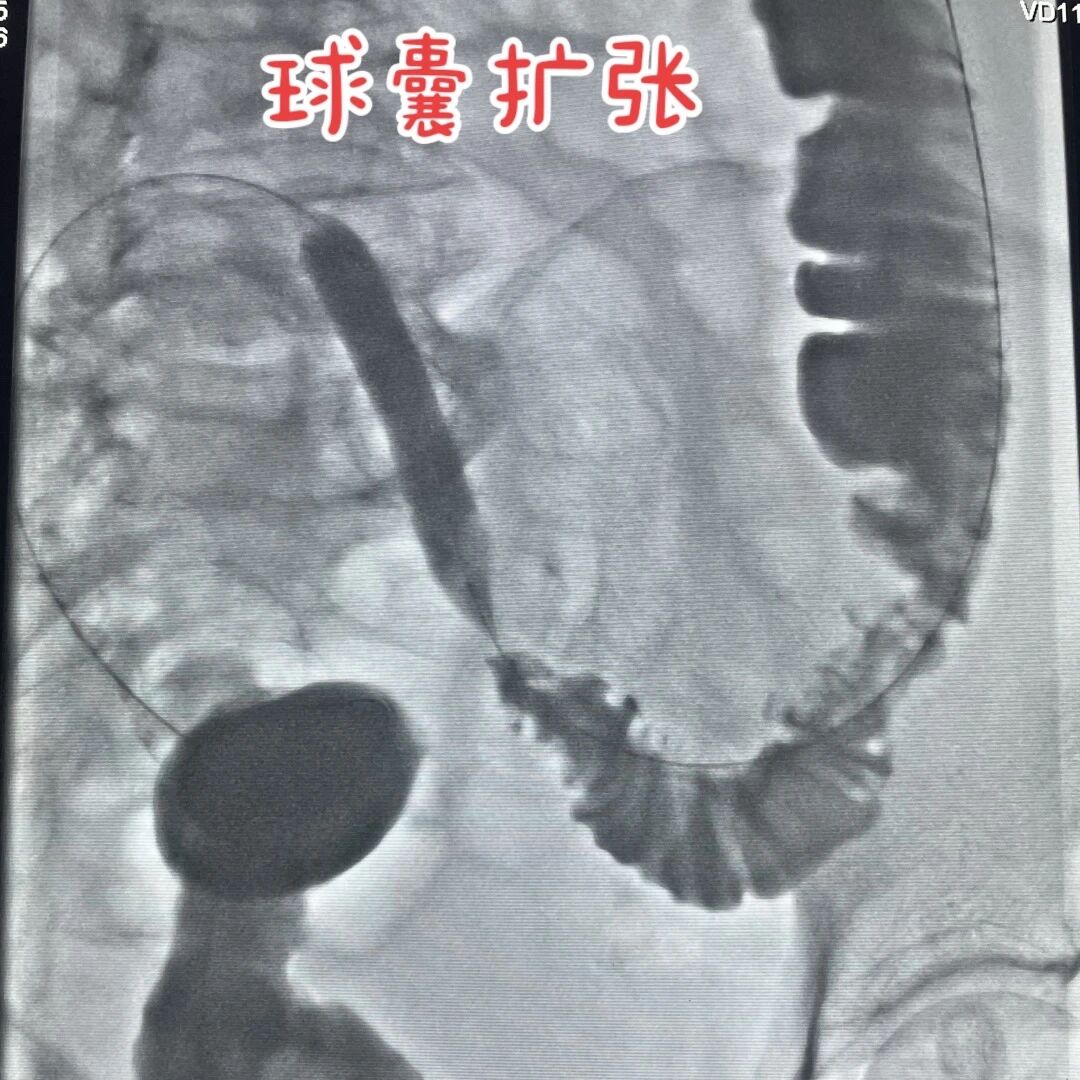

抱着最后一丝希望,家人带着潘婆婆来到西南医科大学附属中医医院。急诊科医生了解情况后,立刻将她转到介入・血管科,斯光晏教授团队赶紧给潘婆婆做了全面检查,又耐心听了她的顾虑,最后给出了一个新方案:“不用开腹,放个肠道支架就行,就像给肠道撑把‘伞’,把堵的地方撑开。”

完善术前准备后,徐燕能博士小心翼翼地从肛门把肠道支架送到梗阻点,慢慢撑开来,把堵塞肠道通道重新打开,让那些被堵住的食物残渣和气体能够顺利通过。整个过程约60分钟,全程全麻,潘婆婆睡了一觉就结束了,一点没觉得疼。